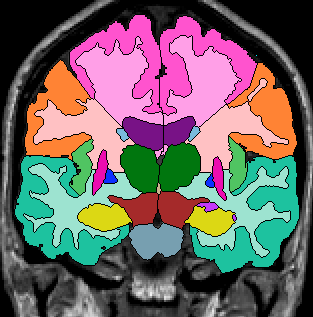

Once you have drawn your sulci lines, the insula should be clearly outlined (by little dots) in the coronal view (Fig 3). This is particularly useful in the more anterior slices.

Figure 3